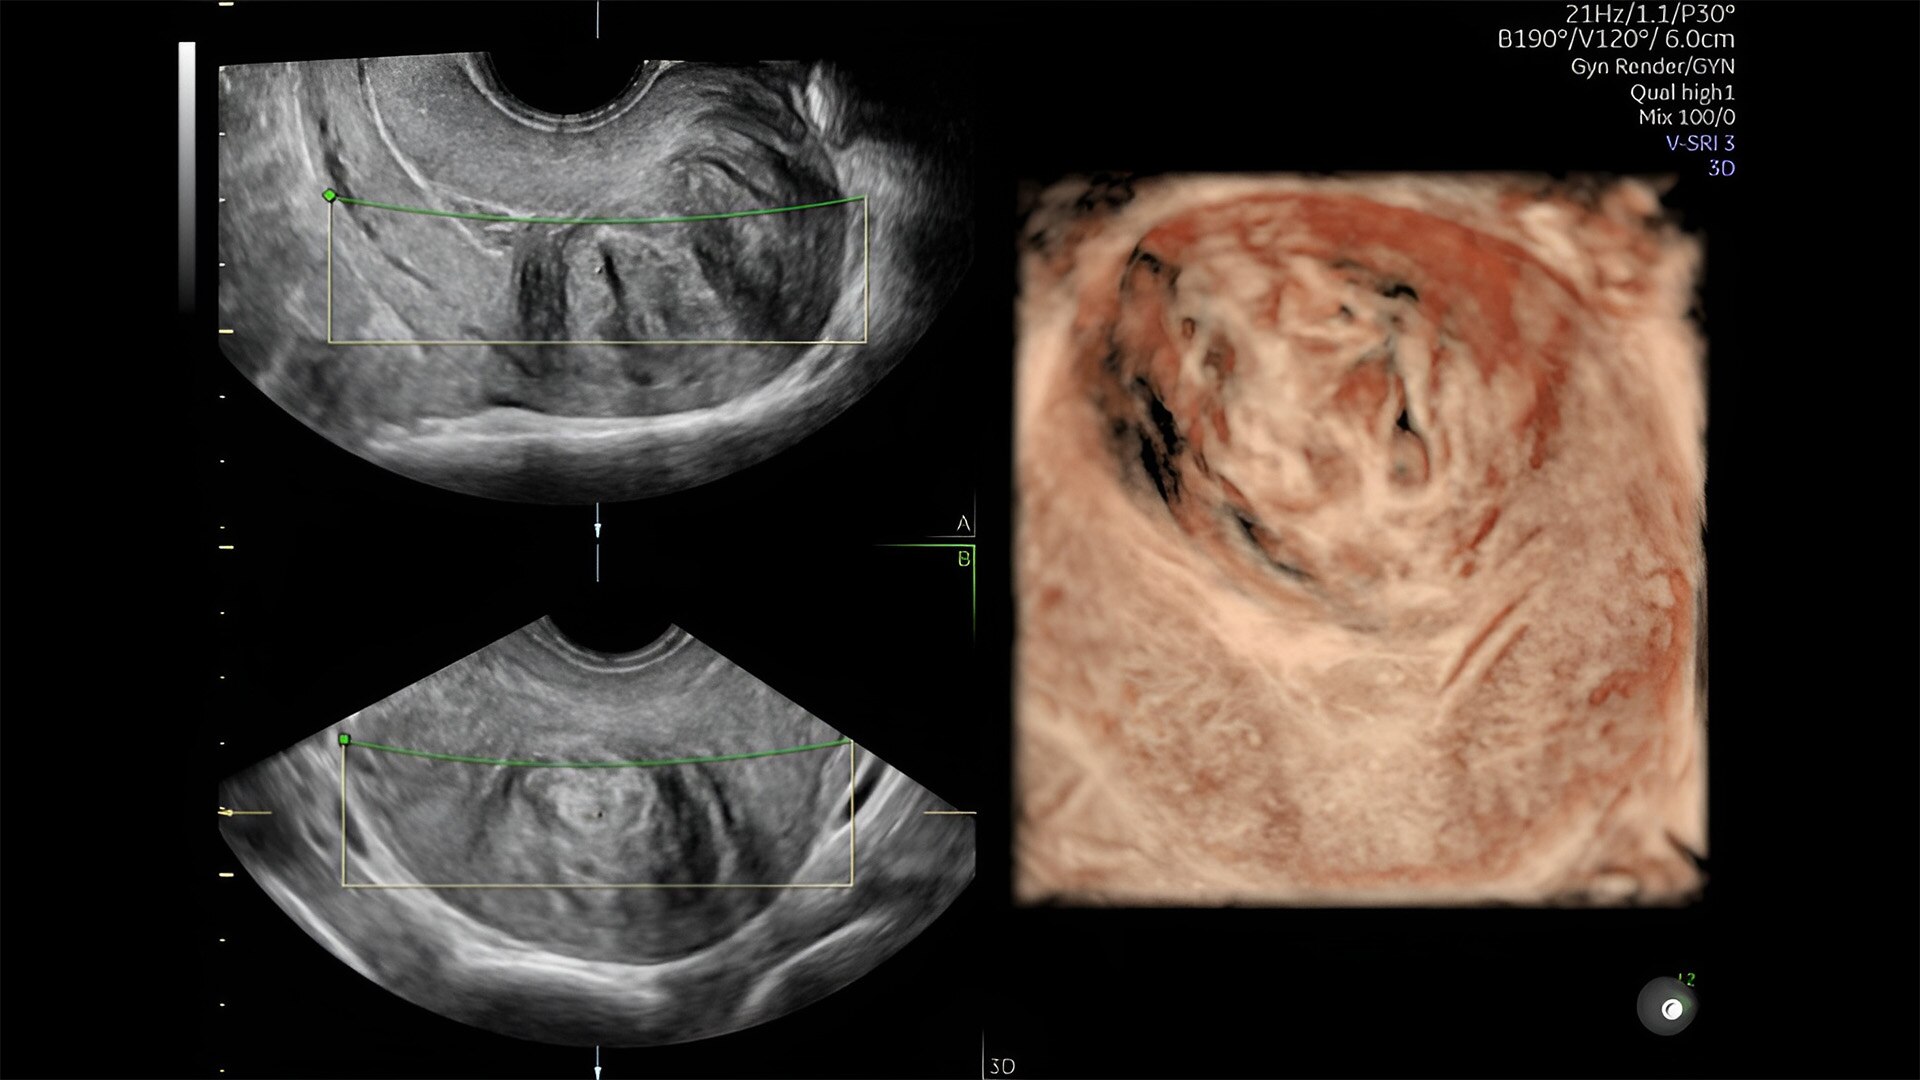

Pelvic health

Offer patient answers faster with Ai-based automation tools